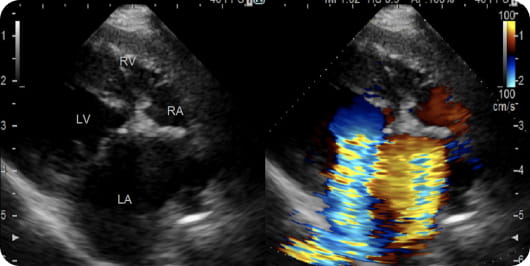

心エコー:心臓手術前の心臓は腱索が伸長・断裂し僧帽弁がうまく閉じずに血液の逆流がある